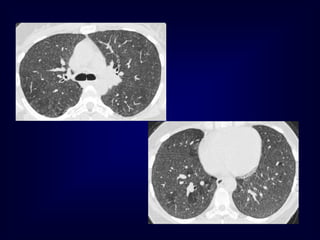

UIP UIP or NSIP

Usual Interstitial Pneumonia UIP

HRCT Findings

Reticular opacities, thickened intra- and

interlobular septa

Irregular interfaces

Honey combing and parenchymal distorsion

Ground glass opacities (never prominent)

Basal and subpleural predominance

Basal and subpleural distribution

UIP

The Many ‘HRCT Faces’ of NSIP

Honeycombing not a

prominent feature !!!!